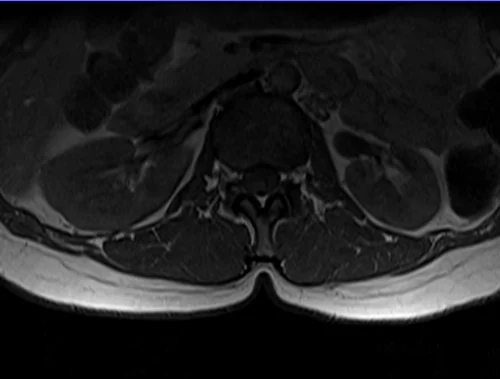

L plexus mri T1 axial images